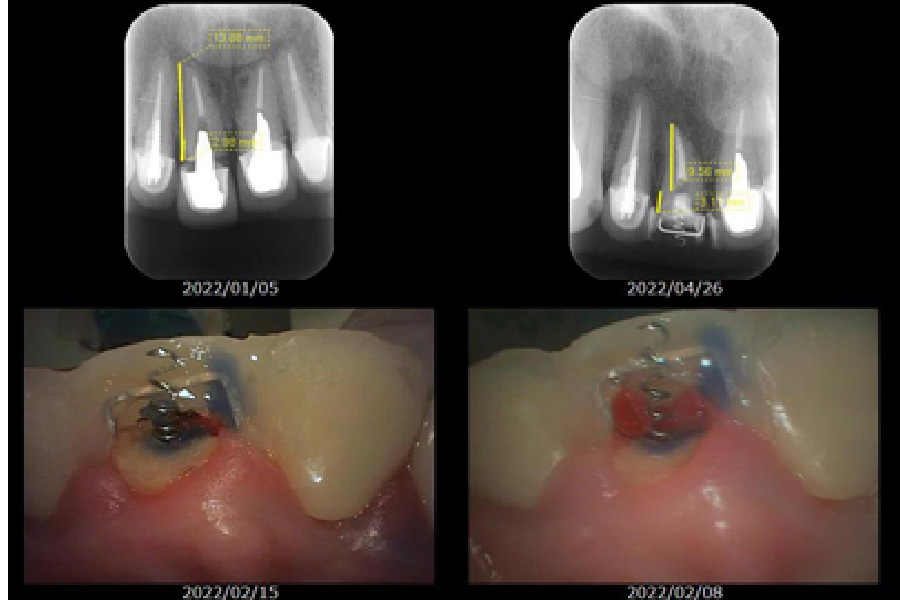

救歯とは、虫歯や歯周病などでダメージを受けた歯を可能な限り抜かずに保存し、機能を回復させる歯科治療です。当院ではBTAテクニック(救歯)で、セラミックと歯肉を付着させ細菌が入りこむスペースを無くし、安定した厚みを持った歯肉で歯の保存を行います。また、歯肉の下の健康な歯質を引っ張り出し、修復を可能にする抜歯回避の手段も行なっております。